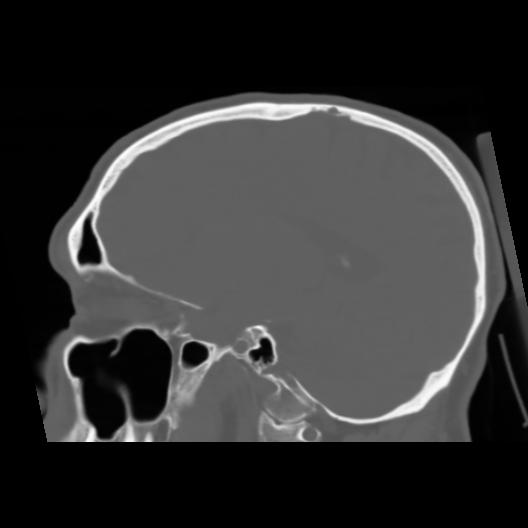

6 CEREBRO,,Sagittal,3.000,CEREBRO,Sagittal,